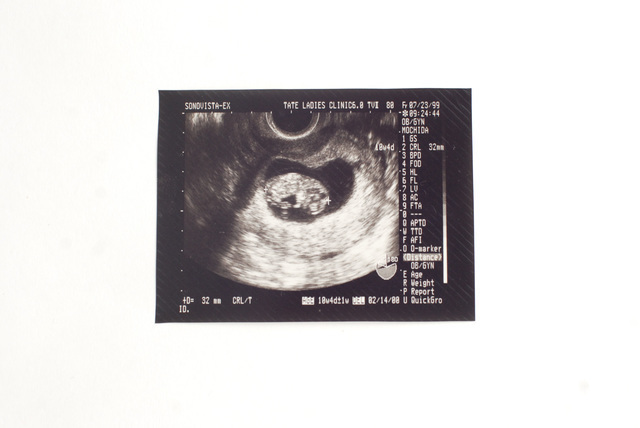

妊娠12週未満での人工妊娠中絶を指します。子宮の中身を掻き出す手術によって中絶を行います。手術については後でお話しします。

妊娠12週から妊娠22週未満での人工妊娠中絶を指します。妊娠初期とは異なり、手術ではなく分娩の形で中絶するため、母体にかかる負担が大きくなります。